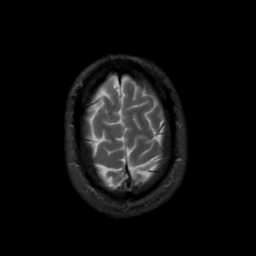

MR Study #4, March 3, 1991 -- Slice #44

[Home][Help][Clinical][Tour 1][Tour 2] Slice 44